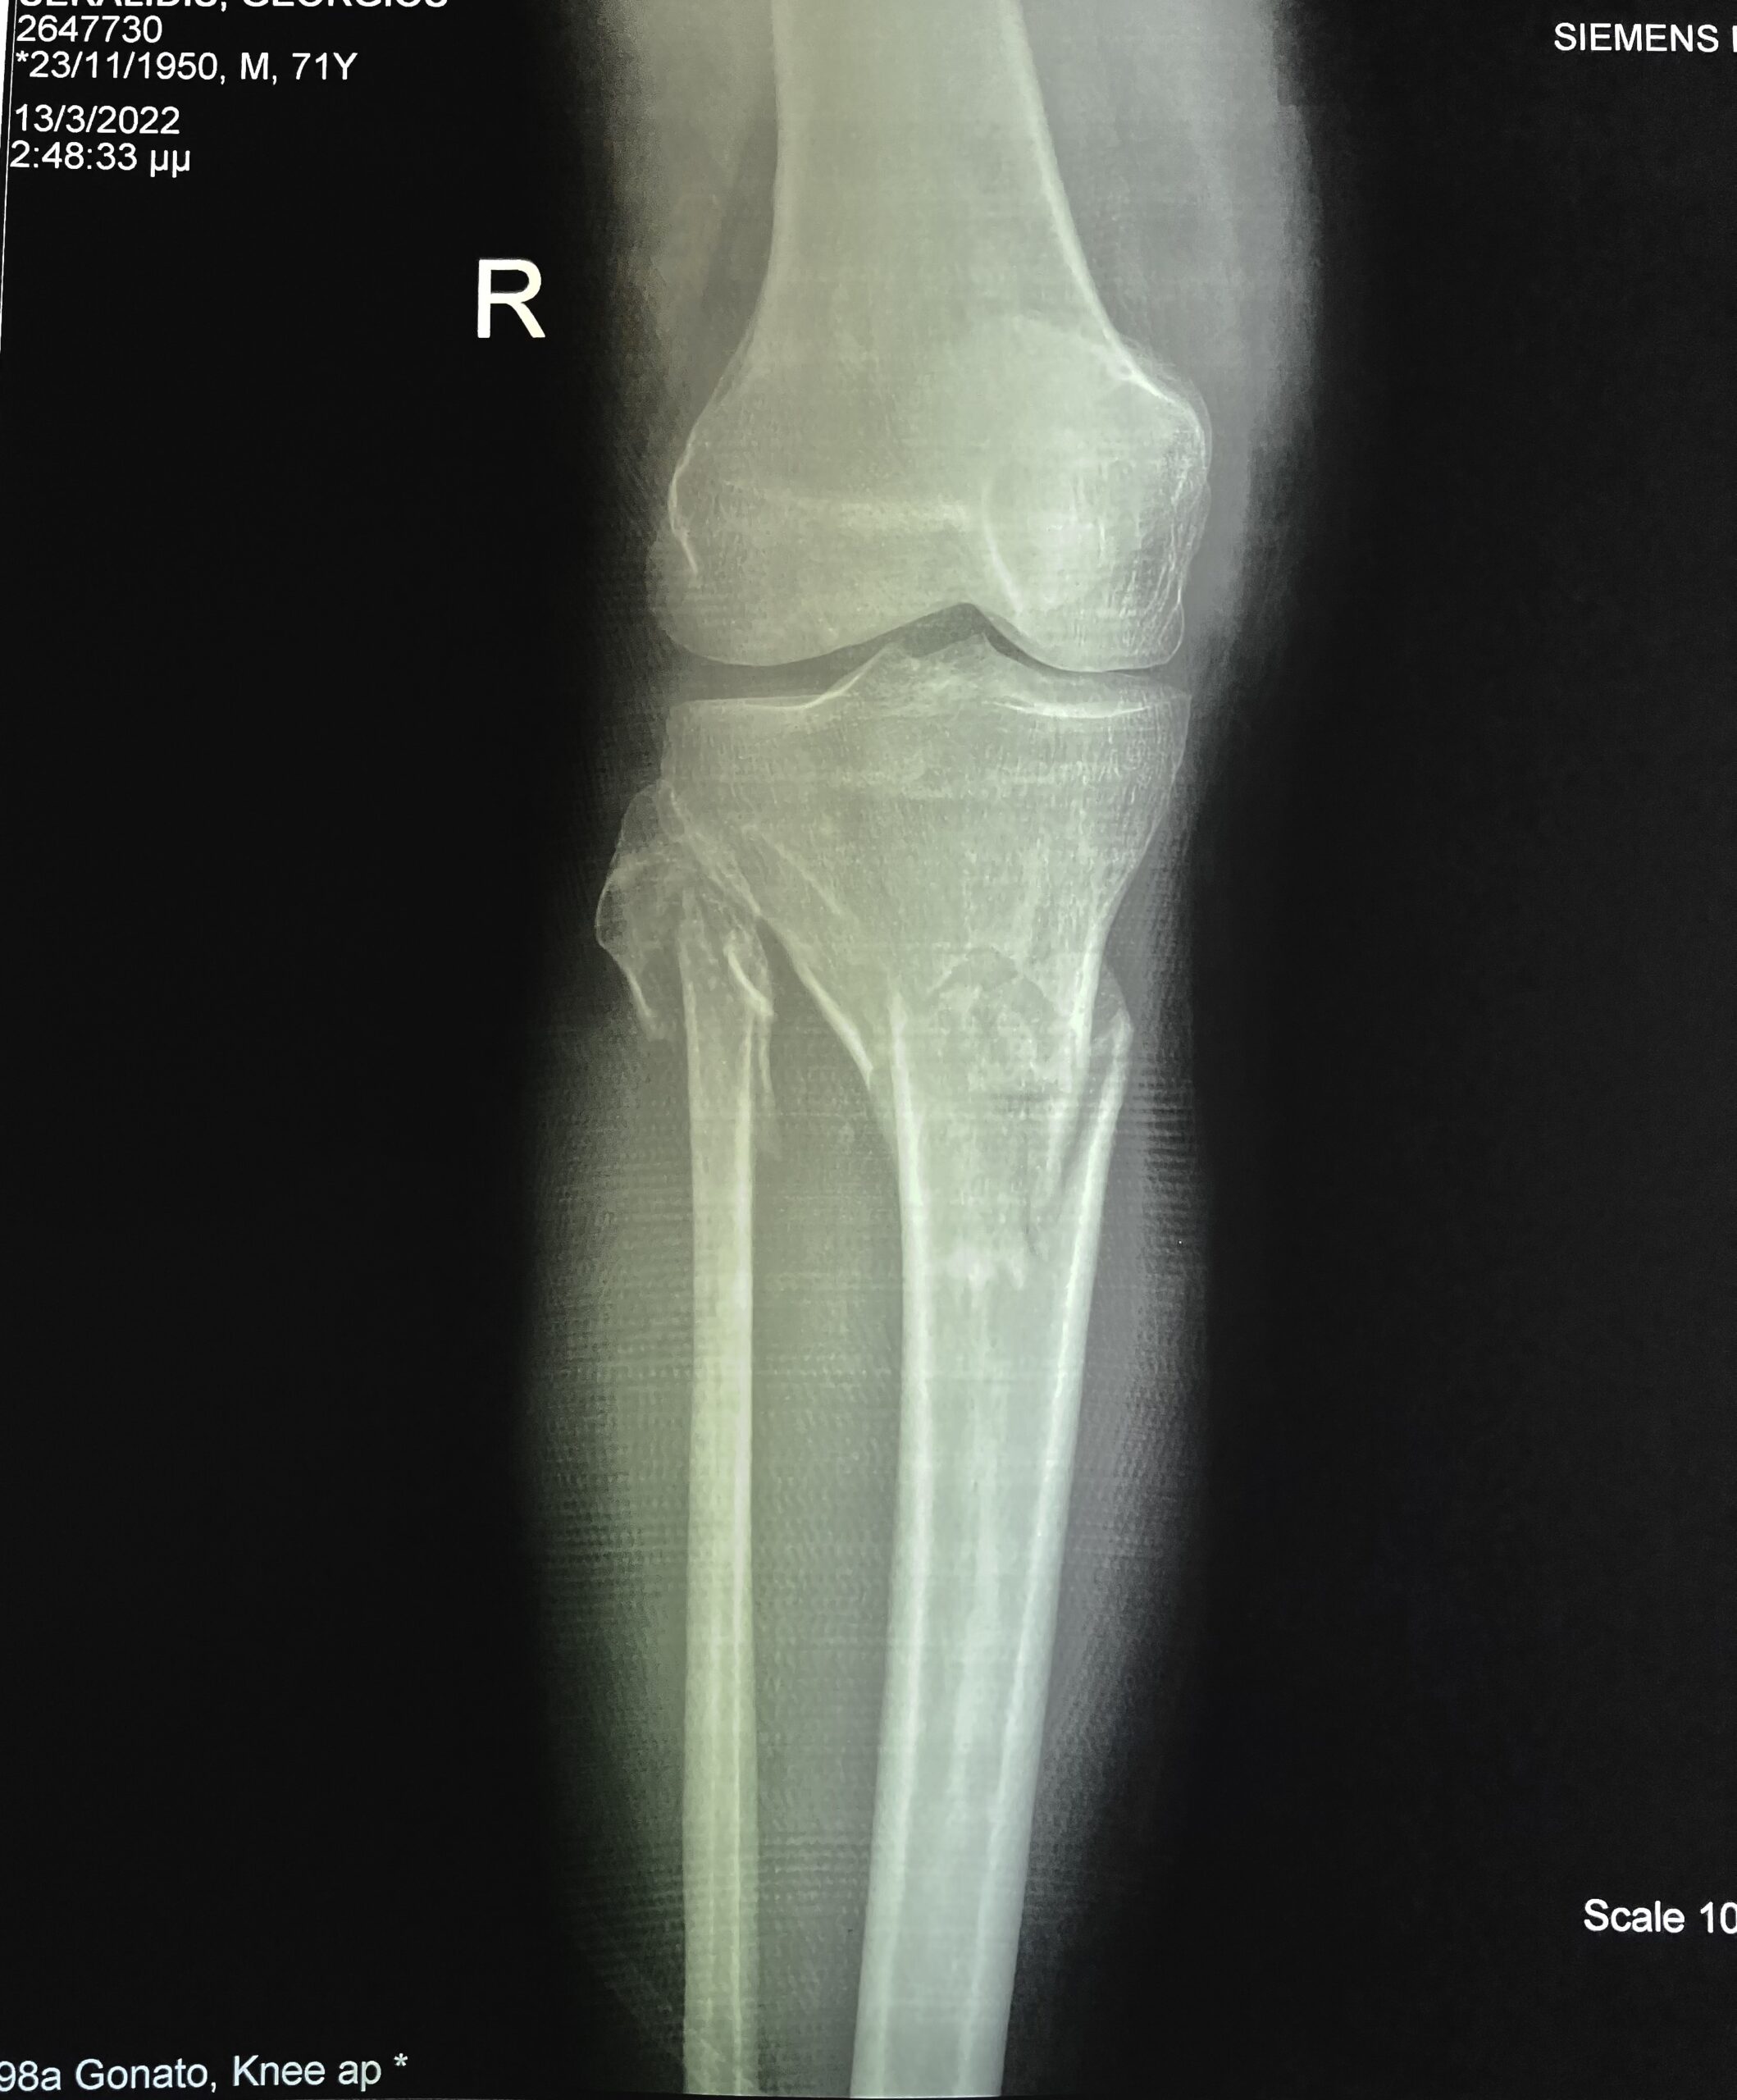

Η διάγνωση ενός κατάγματος κνημιαίου plateau πραγματοποιείται από έναν έμπειρο Ορθοπαιδικό. Αρχικά η λήψη ενός λεπτομερούς ιστορικού και η κλινική εξέταση του ασθενούς είναι απαραίτητα. Στην συνέχεια για την διάγνωση αλλά και την ταξινόμηση του κατάγματος είναι υποχρεωτική η διενέργεια ακτινολογικού ελέγχου. Ο έλεγχος αυτός περιλαμβάνει απλές ακτινογραφίες (φας, προφιλ και λοξές) ενώ πολλές φορές απαιτείται περαιτέρω διερεύνηση με αξονική τομογραφία για την πλήρη κατανόηση της μορφής του κατάγματος και τον σωστό προεγχειρητικό σχεδιασμό.

Ως κάταγμα του κνημιαίου plateau ορίζεται το κάταγμα του ανώτερου τμήματος της κνήμης . Το κνημιαίο plateau (πλατώ) είναι το ανώτερο τμήμα του οστού της κνήμης και ανατομικά αποτελείται από τον έσω και τον έξω κνημιαίο κόνδυλο. Μαζί με το κατώτερο τμήμα του μηρού και την επογονατίδα, σχηματίζουν την άρθρωση του γόνατος. Τα κατάγματα στο συγκεκριμένο σημείο είνα σπάνια, καθώς αφορούν μόνο το 1% των συνολικών καταγμάτων και σε αυτά μπορεί να συμμετέχει ο έσω κόνδυλος, ο έξω κόνδυλος ή και οι δύο (αμφοτερόπλευρα).

Ένα κάταγμα κνημιαίου plateau προκαλείται συνήθως από τραυματισμούς υψηλής ενέργειας, όπως για παράδειγμα τα τροχαία ατυχήματα ή πτώσεις από μεγάλο ύψος. Επίσης κατάγματα κνημιαίου plateau μπορεί να συμβούν και κατά τη διάρκεια αθλητικών δραστηριοτήτων, όπως είναι το ποδόσφαιρο.

Στις μεγαλύτερες ηλικίες για την εκδήλωση των καταγμάτων κνημιαίου plateau ενδέχεται να ευθύνονται παθήσεις των οστών, όπως για παράδειγμα η οστεοπόρωση. Σε αυτές τις περιπτώσεις, το κάταγμα ενδέχεται να προκληθεί ακόμη και από τραυματισμούς χαμηλής ενέργειας.